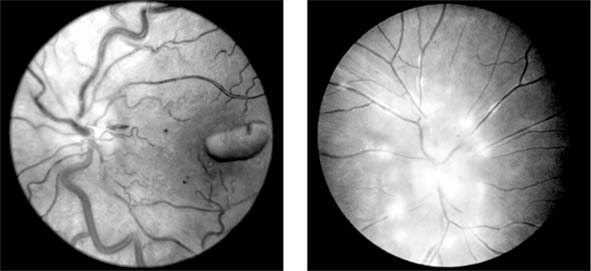

SARCOIDOSIS (new window  Figures 15-25 and new window  15-26)

Sarcoidosis is a multisystem disease with pulmonary, ocular (uveitis), cutaneous, and reticuloendothelial system manifestations. A granulomatous uveitis may be accompanied by cells in the vitreous periphlebitis, disk swelling, retinal neovascularization, and choroidal disease. New vessels may require photocoagulation. The systemic disease is controlled by the administration of oral corticosteroids and occasionally immunosuppressants. Infiltrative optic neuropathy is a rare cause of progressive severe visual loss.

Figure 15-25

Figure 15-25: Sarcoidosis. Focal periphlebitis and disk leakage may respond dramatically to systemic corticosteroids. Left: Before treatment. Right: After 6 weeks of treatment with prednisolone, 30 mg daily.

Figure 15-26

Figure 15-26: Sarcoidosis. Retinal pigment epithelial and choroidal disease may be very distinctive (left) and highlighted by fluorescein angiography (right).